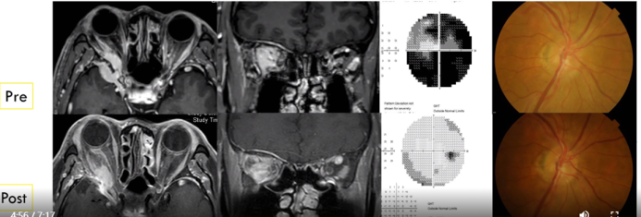

案例分享:37岁女性患者,左眼视力丧失2个月。对高剂量IV甾体类药物调节无效。眼科检查:视力:右1.0 左CF/30cm。EOM:WNL。左眼RAPD(+)。影像学检查见下图(左)。经鼻内窥镜肿瘤切除术后3年,调节效果见下图(右)。